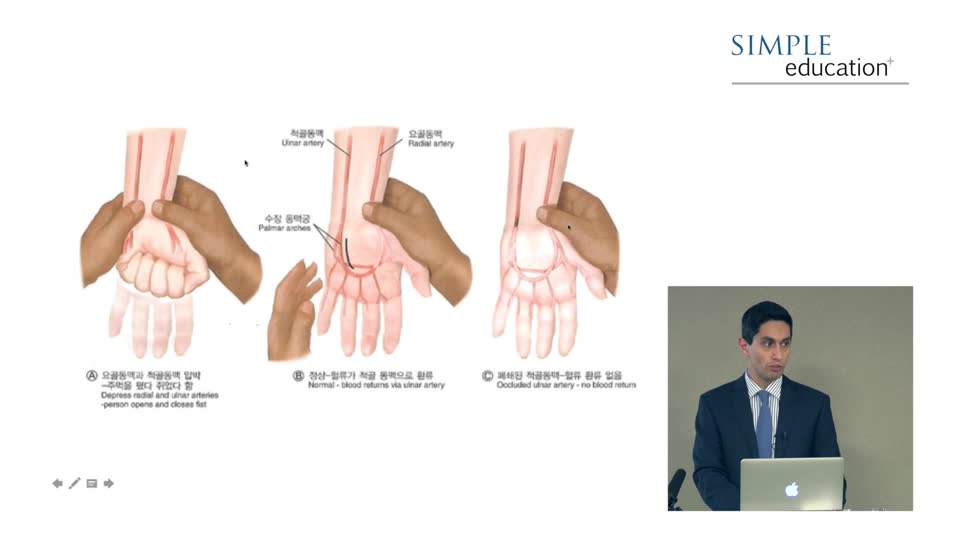

Fail Safe Guide to Access Routes and Guide Catheters in Acutely Unwell Patients - Dr. Amarjit Sethi